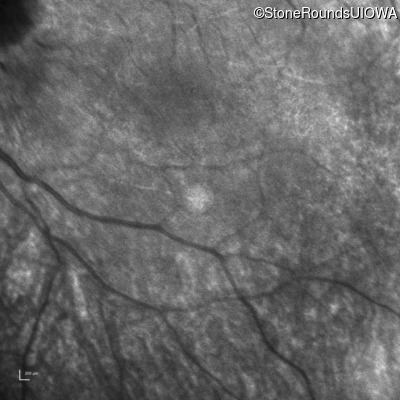

Infrared Fundus Photograph - Left -

No Light Perception

Exemplar

Expanded OCT Stack

×